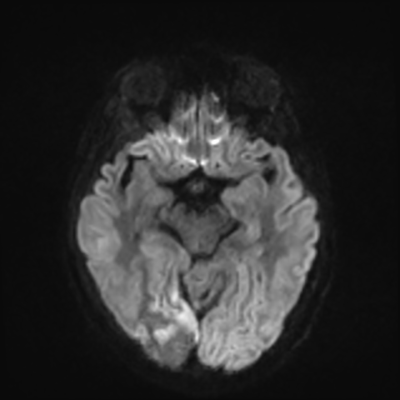

MRI brain (DWI)

You can clearly see diffuse cortical and basal ganglia diffusion restriction, and that of his deep cerebellar nuclei as well. The right occipital lobe abnormalities are a little more prominent, but then you remember that he is known to have had a right occipital stroke weeks ago.